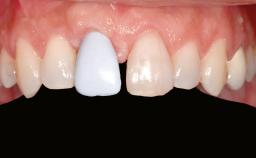

A 20-year-old woman was referred for implant therapy in 2004. Her medical history revealed no significant findings, and neither did she smoke nor take any medications. An extraoral examination revealed no abnormalities of the skin, hair or nails. The intraoral examination revealed only 11 permanent teeth clinically. These were normal in shape, size, and color. In addition, eight retained deciduous teeth (53, 62, 63, 71, 72, 73, 81, 82) were present. No abnormalities were detected during the general examination. The family history revealed that the patient’s father and two sisters were on record with similar conditions. The clinical examination revealed a thick gingival biotype. No recession of the attached gingiva was noted, but the retained deciduous teeth were mobile and unsightly. As a syndrome had not been diagnosed, the case was categorized as non-syndromic oligodontia.

| Patient's Esthetic Expectations | Low | Medium | High |

| Lip Line | No exposure of papillae | Exposure of papillae | Full exposure of mucosa margin |